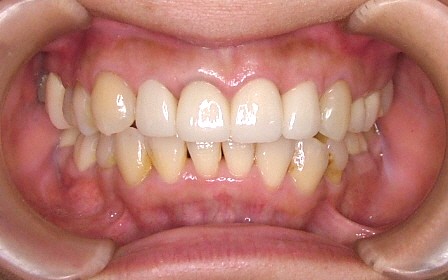

| 治療内容 | ジルコニアセラミック |

|---|---|

| 治療回数 | 3回 |

| 治療時の費用 | 726,000円 ※本症例当時の価格です。最新の費用はこちら |

| リスク・副作用 | 過度なブラシ圧をすると歯肉退縮する可能性があります。 |